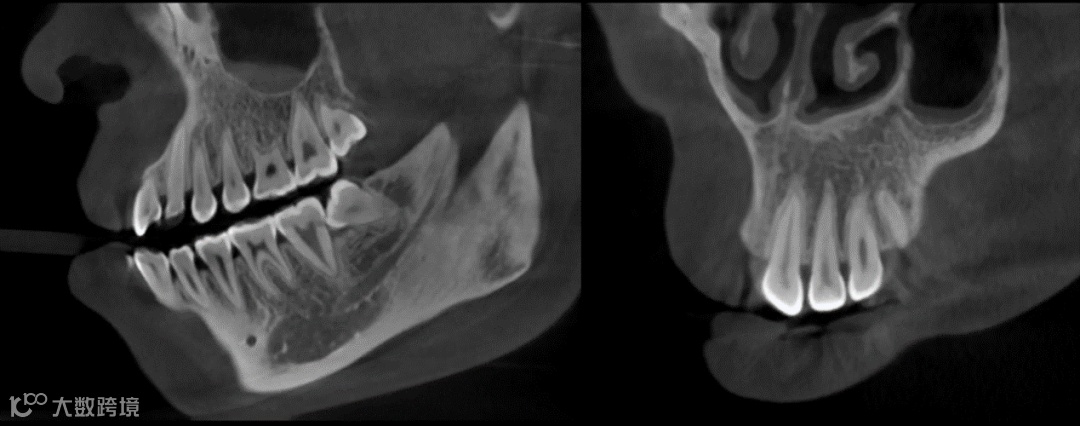

2.图像质量优:菲森采用的东芝球管具有更高的图像分辨率和对比度,能够提供更为清晰、细致的图像。使用的探测器属于行业高端的非晶硅平板,影像高清,噪声低,长期使用也不会使影像质量衰减,这有助于医生进行更准确、细致的诊断和治疗操作。

△菲森CBCT聚焦高清影像